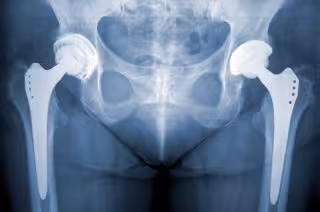

Por qué fallan las prótesis de cadera: Aflojamientos e infecciones

Prótesis de cadera.

Prótesis de cadera. - GETTY IMAGES/ISTOCKPHOTO / NORBERT - Archivo